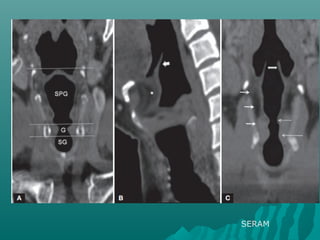

INDICACIONES PARA TEM DEINDICACIONES PARA TEM DE

CUELLOCUELLO

 MODO ESPIRAL PARA ESTUDIOS DEMODO ESPIRAL PARA ESTUDIOS DE

CUELLO DE RUTINA : VG.TUMORES,CUELLO DE RUTINA : VG.TUMORES,

LINFOMA , ABSCESOS ETC.LINFOMA , ABSCESOS ETC.

 UN RANGO DE 15 CM. SE CUBRE ENUN RANGO DE 15 CM. SE CUBRE EN

8.3 SEGUNDOS.8.3 SEGUNDOS.

SERAM

MALFORMACION LINFATICA MACROQUISTICA

ADENOPATIASADENOPATIAS

ABSCESOS